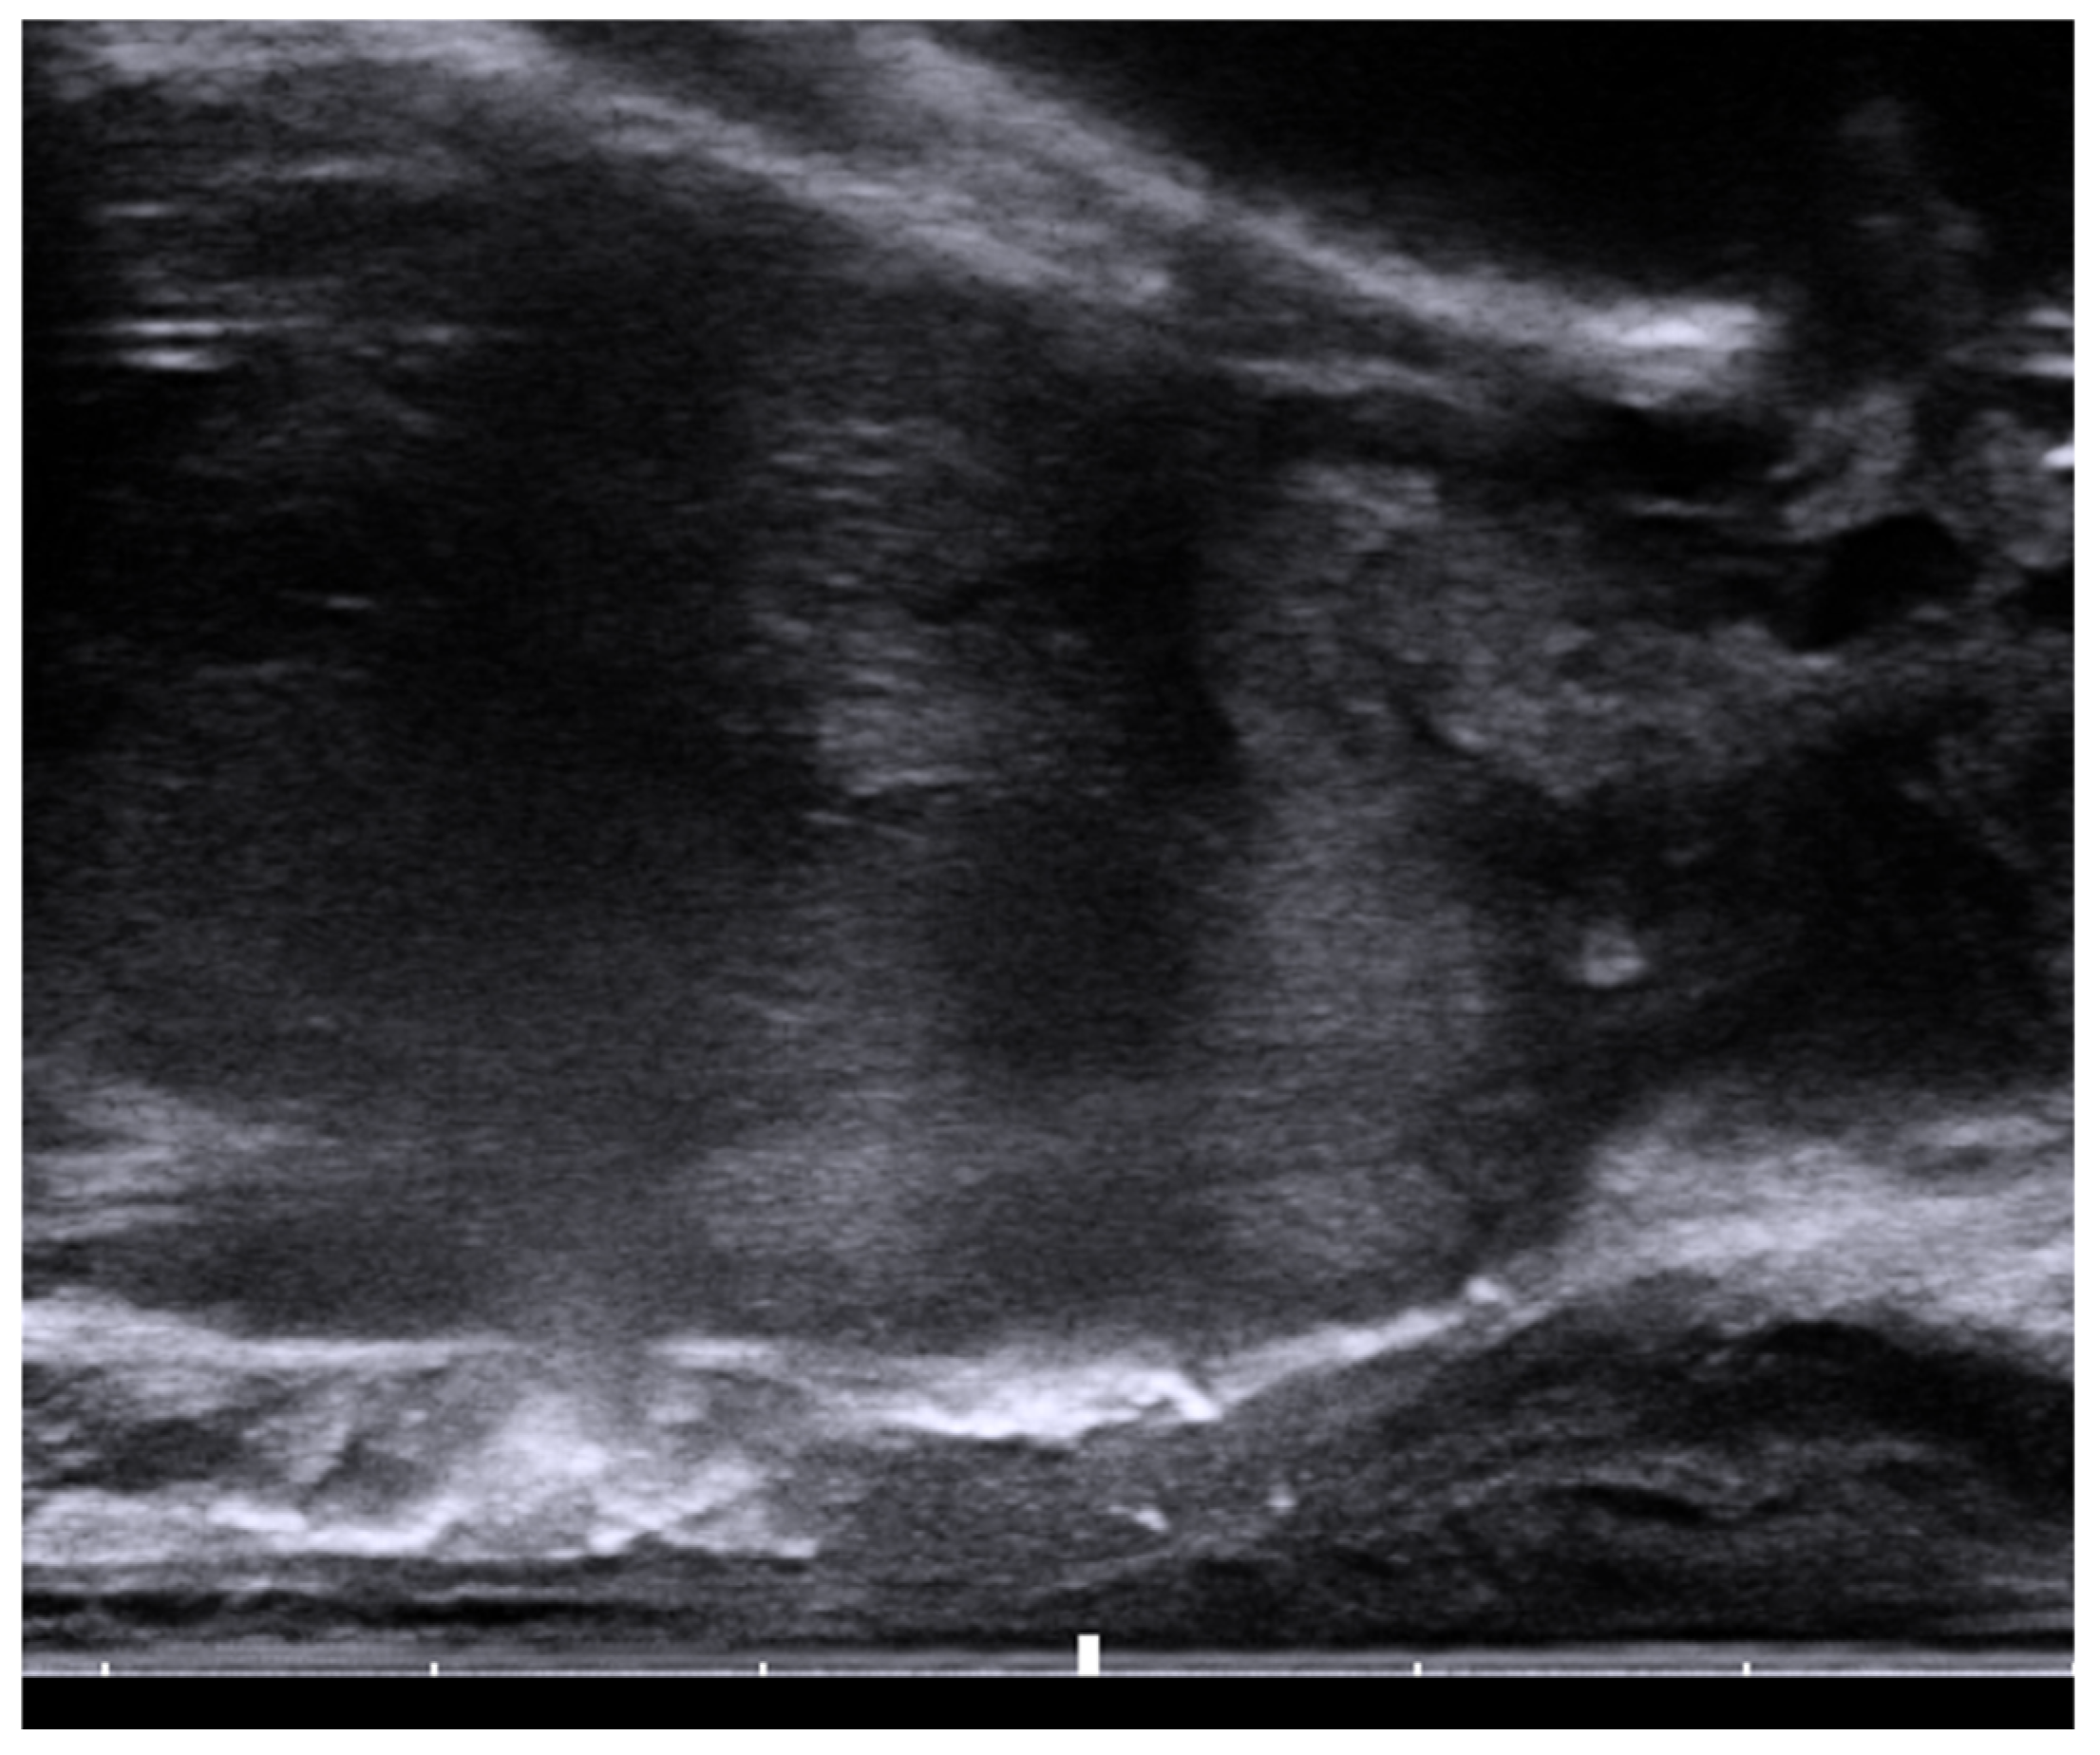

6. Placement

- SpaceOAR™ Vue System. 2022. Available online: https://www.bostonscientific.com/content/dam/bostonscientific/spaceoar/vue/URO-855204-AA%20SpaceOAR%20VUE_Brief%20Summary.pdf (accessed on 9 August 2022).

- SpaceOAR Vue™ Hydrogel. 2020. Available online: https://www.bostonscientific.com/content/dam/bostonscientific/spaceoar/vue/SpaceOAR-Vue-Hydrogel-Brochure.pdf (accessed on 9 August 2022).